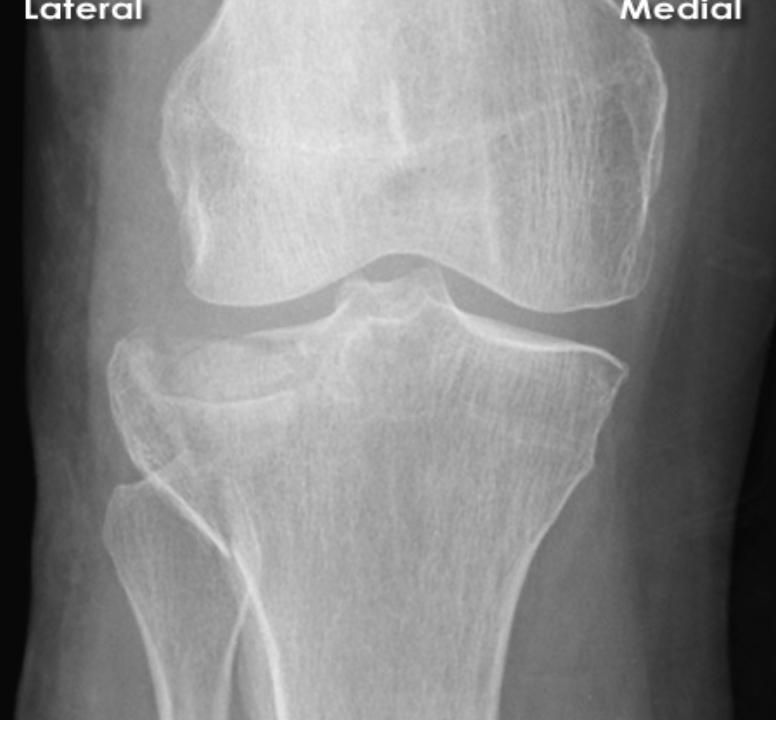

Describe the fracture seen in this X-ray [1]

Lateral tibial plateau fracture

* The fracture fragment is displaced and depressed from its normal position (dotted line)